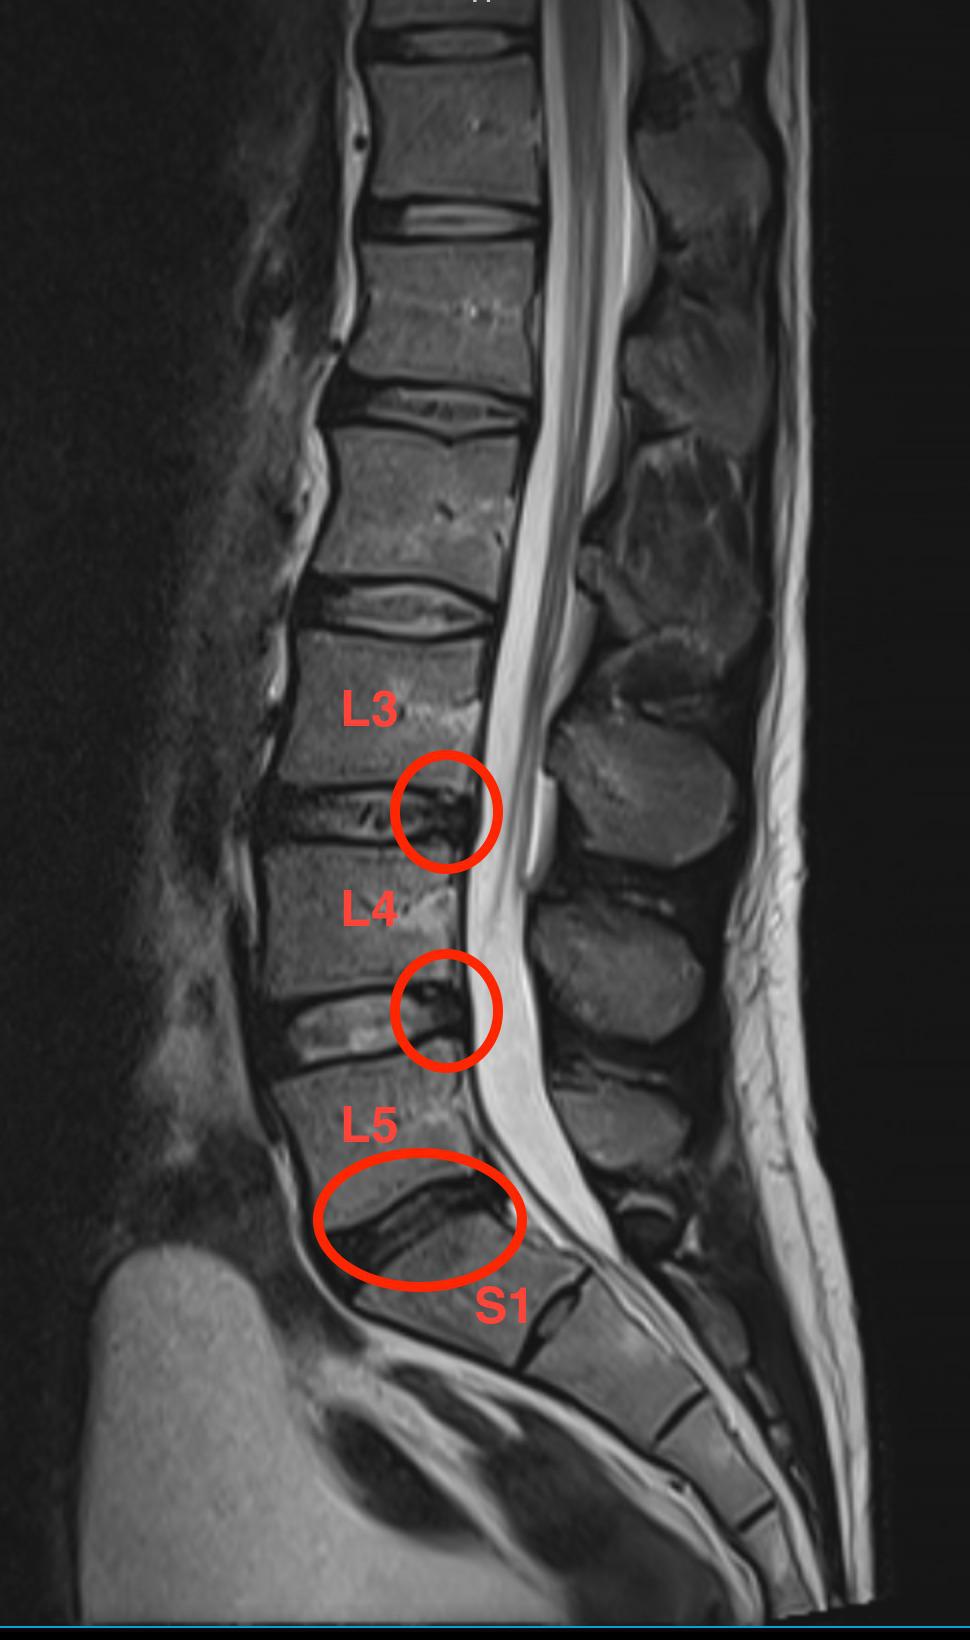

Диск L5 S1 Фото

Диск L5 S1 Фото 115 фотографий